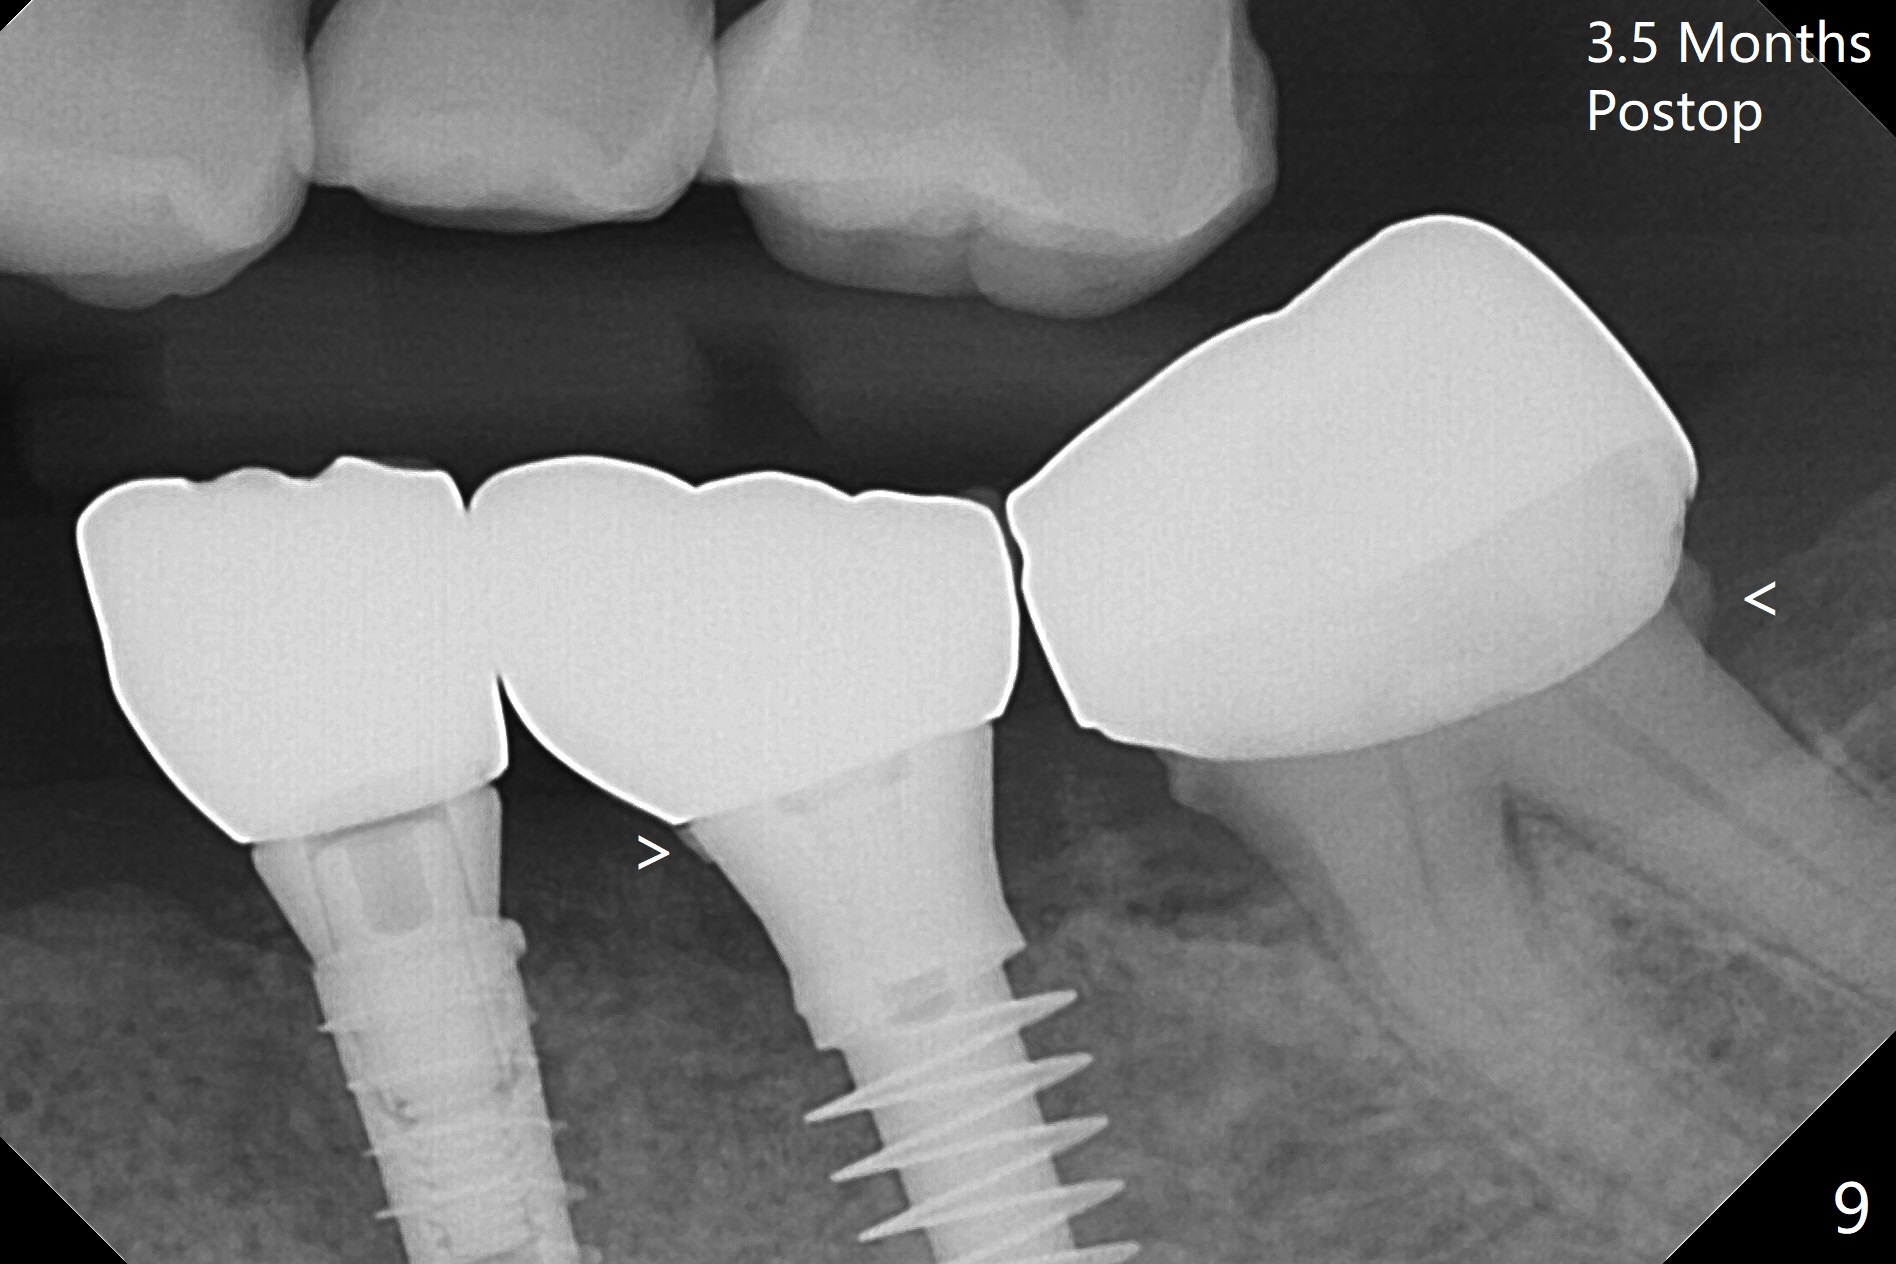

There is no bone loss at #20 or 19 six and 3 months postop, respectively (Fig.6,7). After placing and trimming a 4.3x3 mm Magicore solid abutment, impression is taken (Fig.8). After cementation for #19 and 20 crowns, the crown of #20 is removed for cement removal; attention is paid to cement removal around the crown at #19. In fact, the removal is ineffective with the crown of #20 is reseated and retightened (Fig.9 >). Repeated removal proves to be futile (Fig.10 >). The most effective method will be to take X-ray immediately after #20 crown removal and reseating without torque so that it will be easier to remove the remaining cement if needed. It may be ok in term of hygiene, since proximal brush is used daily. While the crowns at #18 and 19 are being redone because of food impaction, the tooth #18 needs RCT; the Magicore seems to have no bone loss 4 months post cementation (Fig.11). CBCT shows that the Magicore seems to have been placed in the middle of the crest 7 months post cementation (Fig.12 (B: buccal)). The gingiva at #19 is apparently healthy 8 months post cementation. The crown at #19 is recemented 10.5 months post cementation (Fig.13).